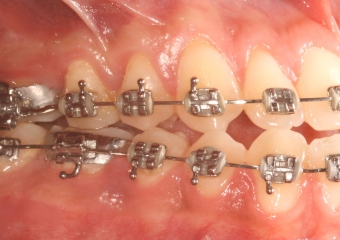

Mordida inicial